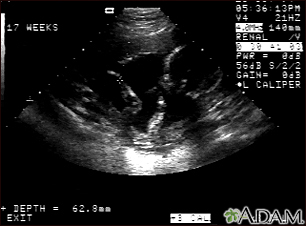

Ultrasound, normal fetus - arm and legs